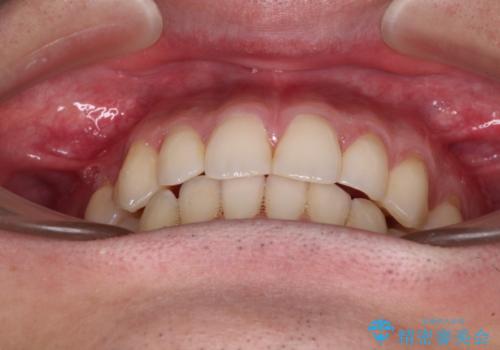

ディープバイトと叢生 インビザラインによる矯正治療

ディープバイトもデコボコも改善され、気になっていた銀歯もセラミックとなり、患者様には大変満足していただきました。

上下ともに叢生が認められたため、親知らずすべてを抜歯し、歯列全体を後方へ移動させることで歯列を整えることとしました。

上顎奥歯の銀歯も気になっていたので、矯正治療の途中でセラミッククラウンへ変更し、その後歯列を仕上げていくこととしました。